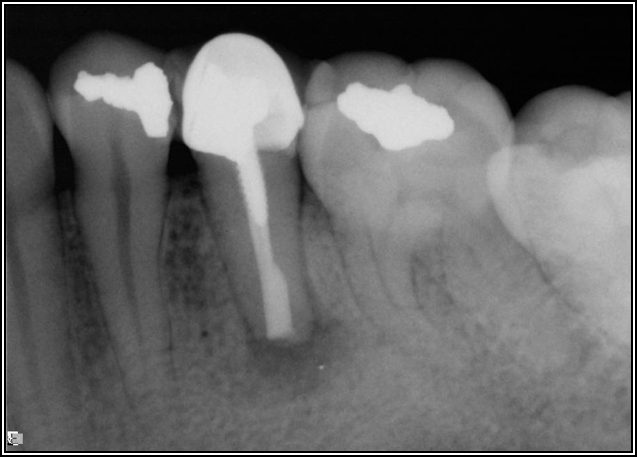

Fig 8. Bitewing revealed decay and other problems.

Figure 8

Occlusal Considerations

Occlusion is one of the most overlooked areas in endodontics; however, other than remaining structure, it is the most important factor.7 Patients who are heavy bruxers can cause the need for a root canal from the lateral forces. Patients who clench pose a different challenge with apical forces, yet the damage from both can be the same. Figure 7 shows a patient with bruxism. The patient had pain in response to hot and cold stimulus, and the clinicians needed a bitewing to determine which tooth was causing the pain. From the periapical (PA), it was clear that tooth No. 2 had a large problem, No. 3 had a crown, and No. 4 had a large restoration. Any of the three may have been the source of the problem.

With the bitewing shown in Figure 8, it became clear there was gross decay in tooth No. 3 that could not be seen on the PA, and there was a periodontal defect, a pulp stone, in No. 2. There was also a class V lesion revealing the bruxism, flat occlusion, multiple restorations in No. 30, a post in No. 31, and decay on No. 2 as well. The post in No. 31 was useless because when a post is placed, it must be the right length, width, and size. If the post is too short, there will be a greater fulcrum and the tooth will break. If it is too long, the clinician can break it by wedging it. If it is too short, it will not hurt the tooth, but it will not provide any valuable function. It is overall preferable to do posts in teeth having just single restorations rather than abutments for bridges because those teeth are already under greater force. If the technique is not performed correctly, iatrogenic issues may result.